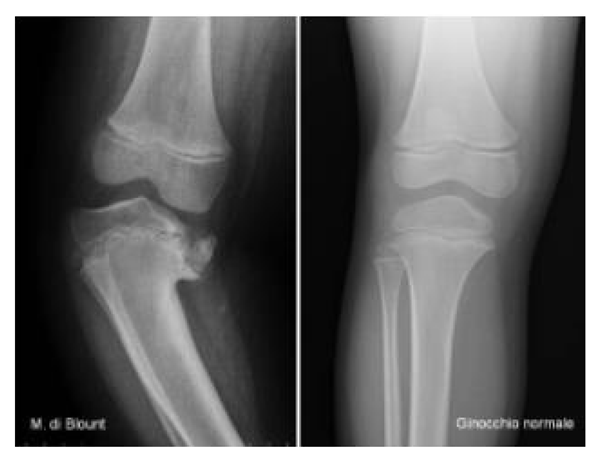

To date, various paths have been designed for the reconstruction of a virtual model of anatomical parts, but the next step in creating a method to fully simulate surgical operations in detail is missing. A valid option is to use dedicated medical software: in “Application of computer simulation in the treatment of traumatic cubitus varus deformity in children” [11] MIMICS is used for the simulation of osteotomy, in “Accuracy of the preoperative planning for cementless total hip arthroplasty” [12] use is made of the Hip-PlanTM software (Symbios, Yverdon, Switzerland), which deals only with hip arthroplasty planning, while in “Integration of CAD/CAM planning into computer assisted orthopaedic surgery” [13] the model is transformed into three dimensions and customized bone prostheses are created for the patient via MIMICS software. Another interesting study is the one presented in the script of Wong et al. (2020) [14], where a novel titanium 3D-printed patient-specific implant, starting from a model made with parametric software, is presented. Additionally, there is the paper of Milojevic et al. (2010) [15] that performs a three-dimensional approximation of a femur from X-ray images to verify the exact position and measurements of the screws which are built-in in the human femur. Some studies of the same nature have been carried out on cadavers to test methods of simulation and realization of customized three-dimensional guides; two examples are the works of Helguero et al. (2015) [16] and Wong et al. (2012) [17]. Research has also developed in other directions by testing soft tissue simulations, such as in the script of Perica et al. (2017), [18] but without particular results. In the work of Cofaru et al. (2018) [19] the authors approach a modular device suitable for the different human knee surgery procedures built through the use of Catia V5R20, a commercial software. In the script of Gómez-Palomo et al. (2020) [20] is described the case of a 26-year-old patient diagnosed with Blount disease and the implementation of relative cutting guides for the surgery with the use of the commercial software Fusion 360.

Seven different cases are reported in this study to verify the effectiveness of the CASS methodology and to identify any criticalities deriving from the great cases of pathology in the orthopedic field (Table 2). For all patients, the processing starts from a computerized tomography examination to obtain an optimized 3D model of the examined anatomy and, finally, the simulation of the surgery on CREO.

Report of the examined pathologies.